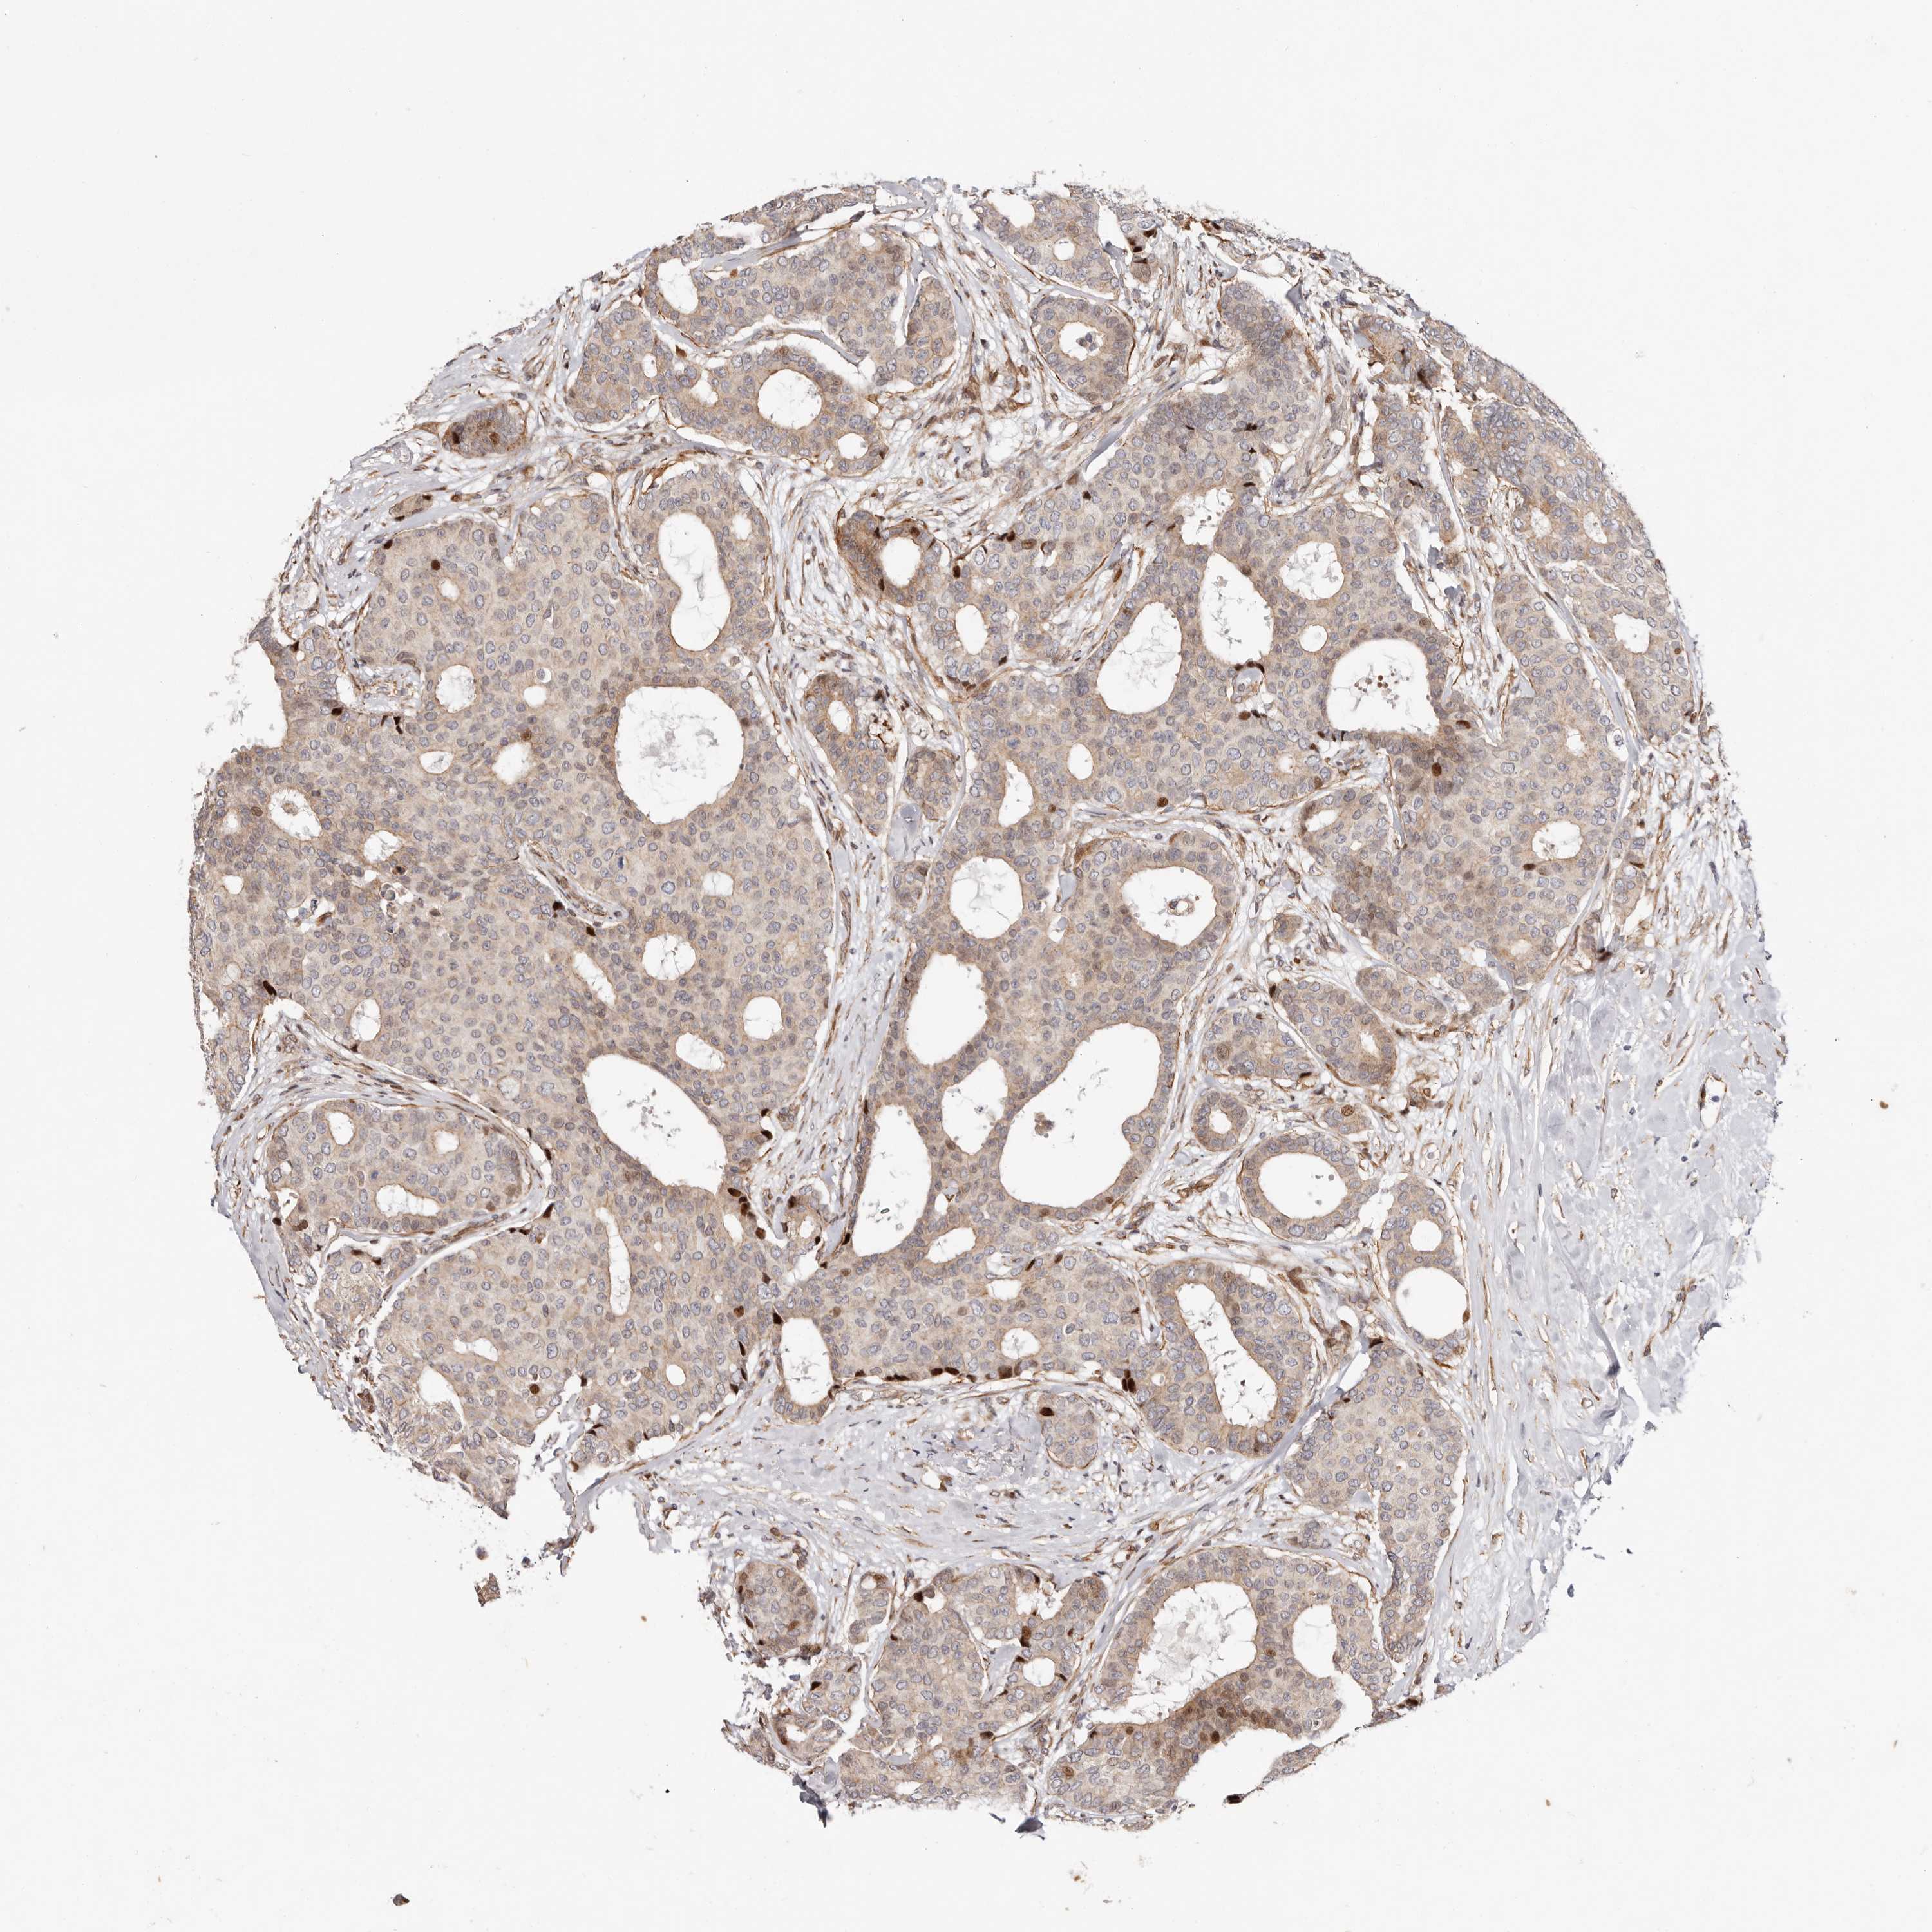

CANCER BREAST CANCER Show tissue menu

BRCA TCGA BRCA VALIDATION PROTEIN EXPRESSION

Breast cancer

Human cancer